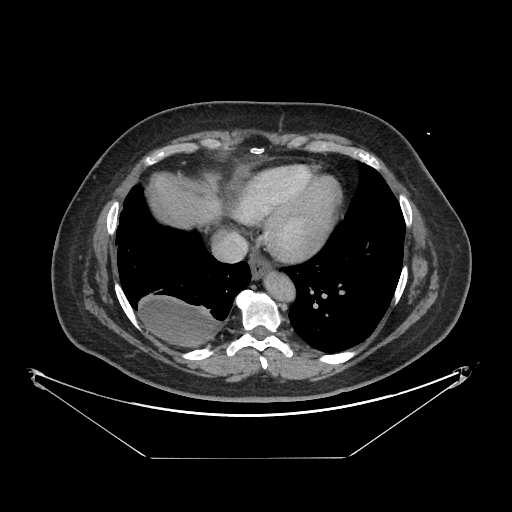

Original NATIVE CT scan (input)

Full window (WL 1023.5, WW 4095 β†’ Low βˆ’1024, High +3071)

Original VENOUS CT scan

Generated VENOUS CT scan (A→B translation)